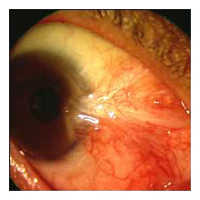

Before Pterygium Removal  After

Pterygium Removal

Pterygium (pronounced "tur-RIDGE-ium")

is a pinkish-yellow, triangular-shaped benign tissue growth starting

from the nasal area of your eye and grows toward the cornea. As

a pterygium grows, it can be varied in its appearance from small

and pink to large and angry red with symptoms of dry eye. Eventually,

it may cause visual disturbances by disrupting the normally smooth

surface of the cornea. In severe cases, a pterygium can block a

patient's vision altogether.